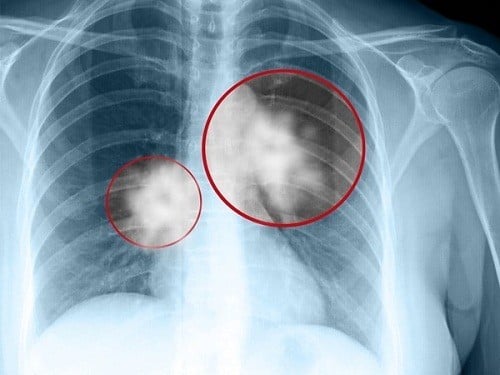

Ung thư phổi sống được bao lâu?

Ung thư phổi sống được bao lâu phụ thuộc chủ yếu vào giai đoạn bệnh. Các yếu tố liên quan khác bao gồm loại ung thư phổi, sức khỏe của người bệnh, khả năng đáp ứng với điều trị, vv…

Ung thư phổi sống được bao lâu phụ thuộc chủ yếu vào giai đoạn bệnh.